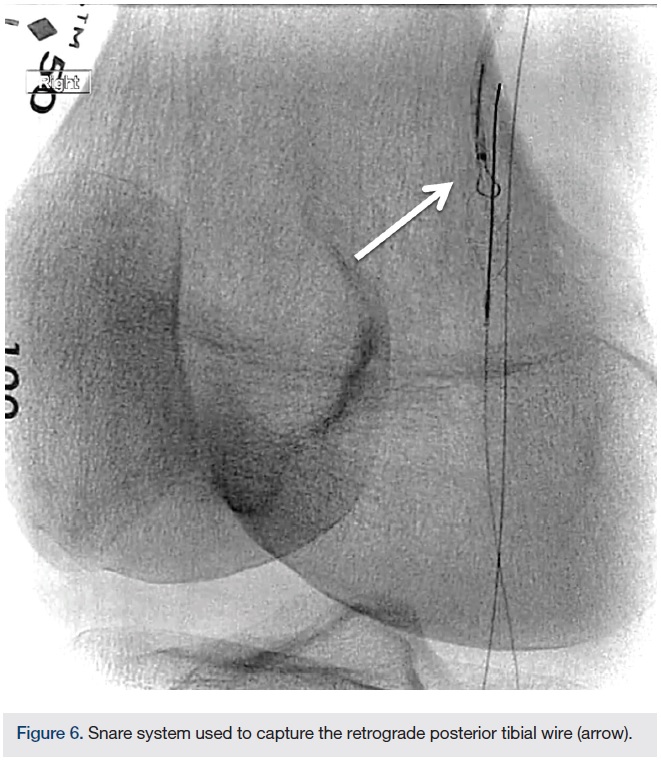

Alternative access. The nature of the occlusion in this case highlights the necessity of alternative access. The lesion extended from the popliteal into the posterior tibial/tibio-peroneal trunk/peroneal arteries. The angiogram showed a flush occlusion of the posterior tibial with reconstitution. Retrograde posterior tibial US-guided access was the only option to gain access into the distal patent portion (Figure 5). We placed a low-profile Cook tibiopedal sheath (2.9 French) (Cook Medical). Using an .018-inch CXI support catheter (Cook Medical), we advanced an .014-inch Glidewire Advantage wire (Terumo). Crossing into the true lumen of the popliteal artery in a retrograde fashion was relatively simple. Using a 7 mm snare, we were able to trap the Glidewire Advantage wire and reverse access (Figure 6). After reversing access, the wire in the posterior tibial artery was now flossed through the sheath. The posterior tibial sheath acted as an embolic protection system. The peroneal artery CTO was crossed in an antegrade fashion and the wire was placed in the distal peroneal artery. An embolic protection device was deployed in the distal peroneal artery. In an effort to protect the distal posterior tibial, we accessed the posterior tibial and crossed the occlusion after performing atherectomy of the popliteal artery. In addition, we did not want to use the larger JETSTREAM device in the popliteal while there was another wire present.